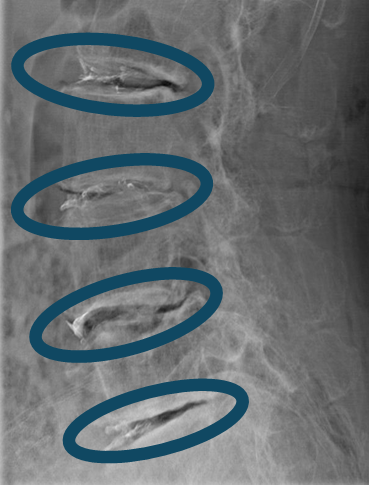

DiscoGelを入れた後の画像になります。